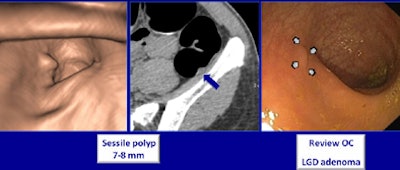

A sessile polyp 7-8 mm missed at optical colonoscopy was seen at CTC and confirmed at repeat colonoscopy. Histology revealed the presence of a low-grade adenoma. All images courtesy of Dr. Philippe Lefere.The idea of bringing CTC to the Portuguese archipelago originated with the University of Madeira, not the Belgian team, Lefere said. Principal investigator Dr. Celso Silva from the university's Clinica de Santa Catarina "wanted to do a screening study comparing optical and virtual colonoscopy, but they did not have local experience," Lefere said. So they approached Lefere's group for help.